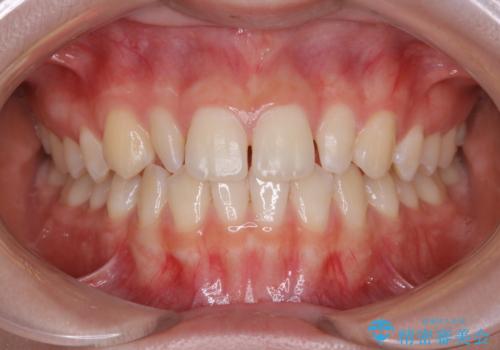

- 初診時、前歯部の見た目の改善を主訴にご来院されました。生まれつき歯が小さい状態の「矮小歯」とそれに伴う正中の「すきっ歯」があるため、大きなガタつきはないものの笑った時の印象に違和感が出る状態となっていました。

矮小歯が傾斜していることなどを踏まえ、より安全に治療を進めるために部分矯正を併用したセラミッククラウンでの治療を行うこととなりました。